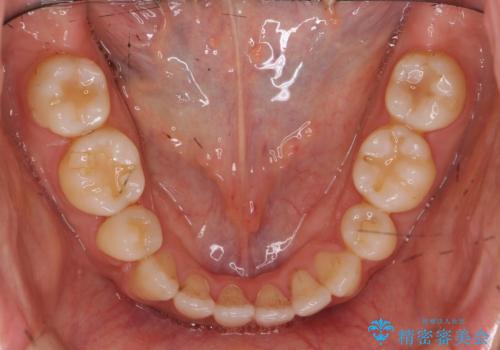

八重歯 上下の正中のずれ 40代で抜歯矯正

- 八重歯と上下の正中のずれを気にして来院。

上の前歯の正中が右にずれていました。

小臼歯抜歯を行い、ワイヤー矯正を行いました。